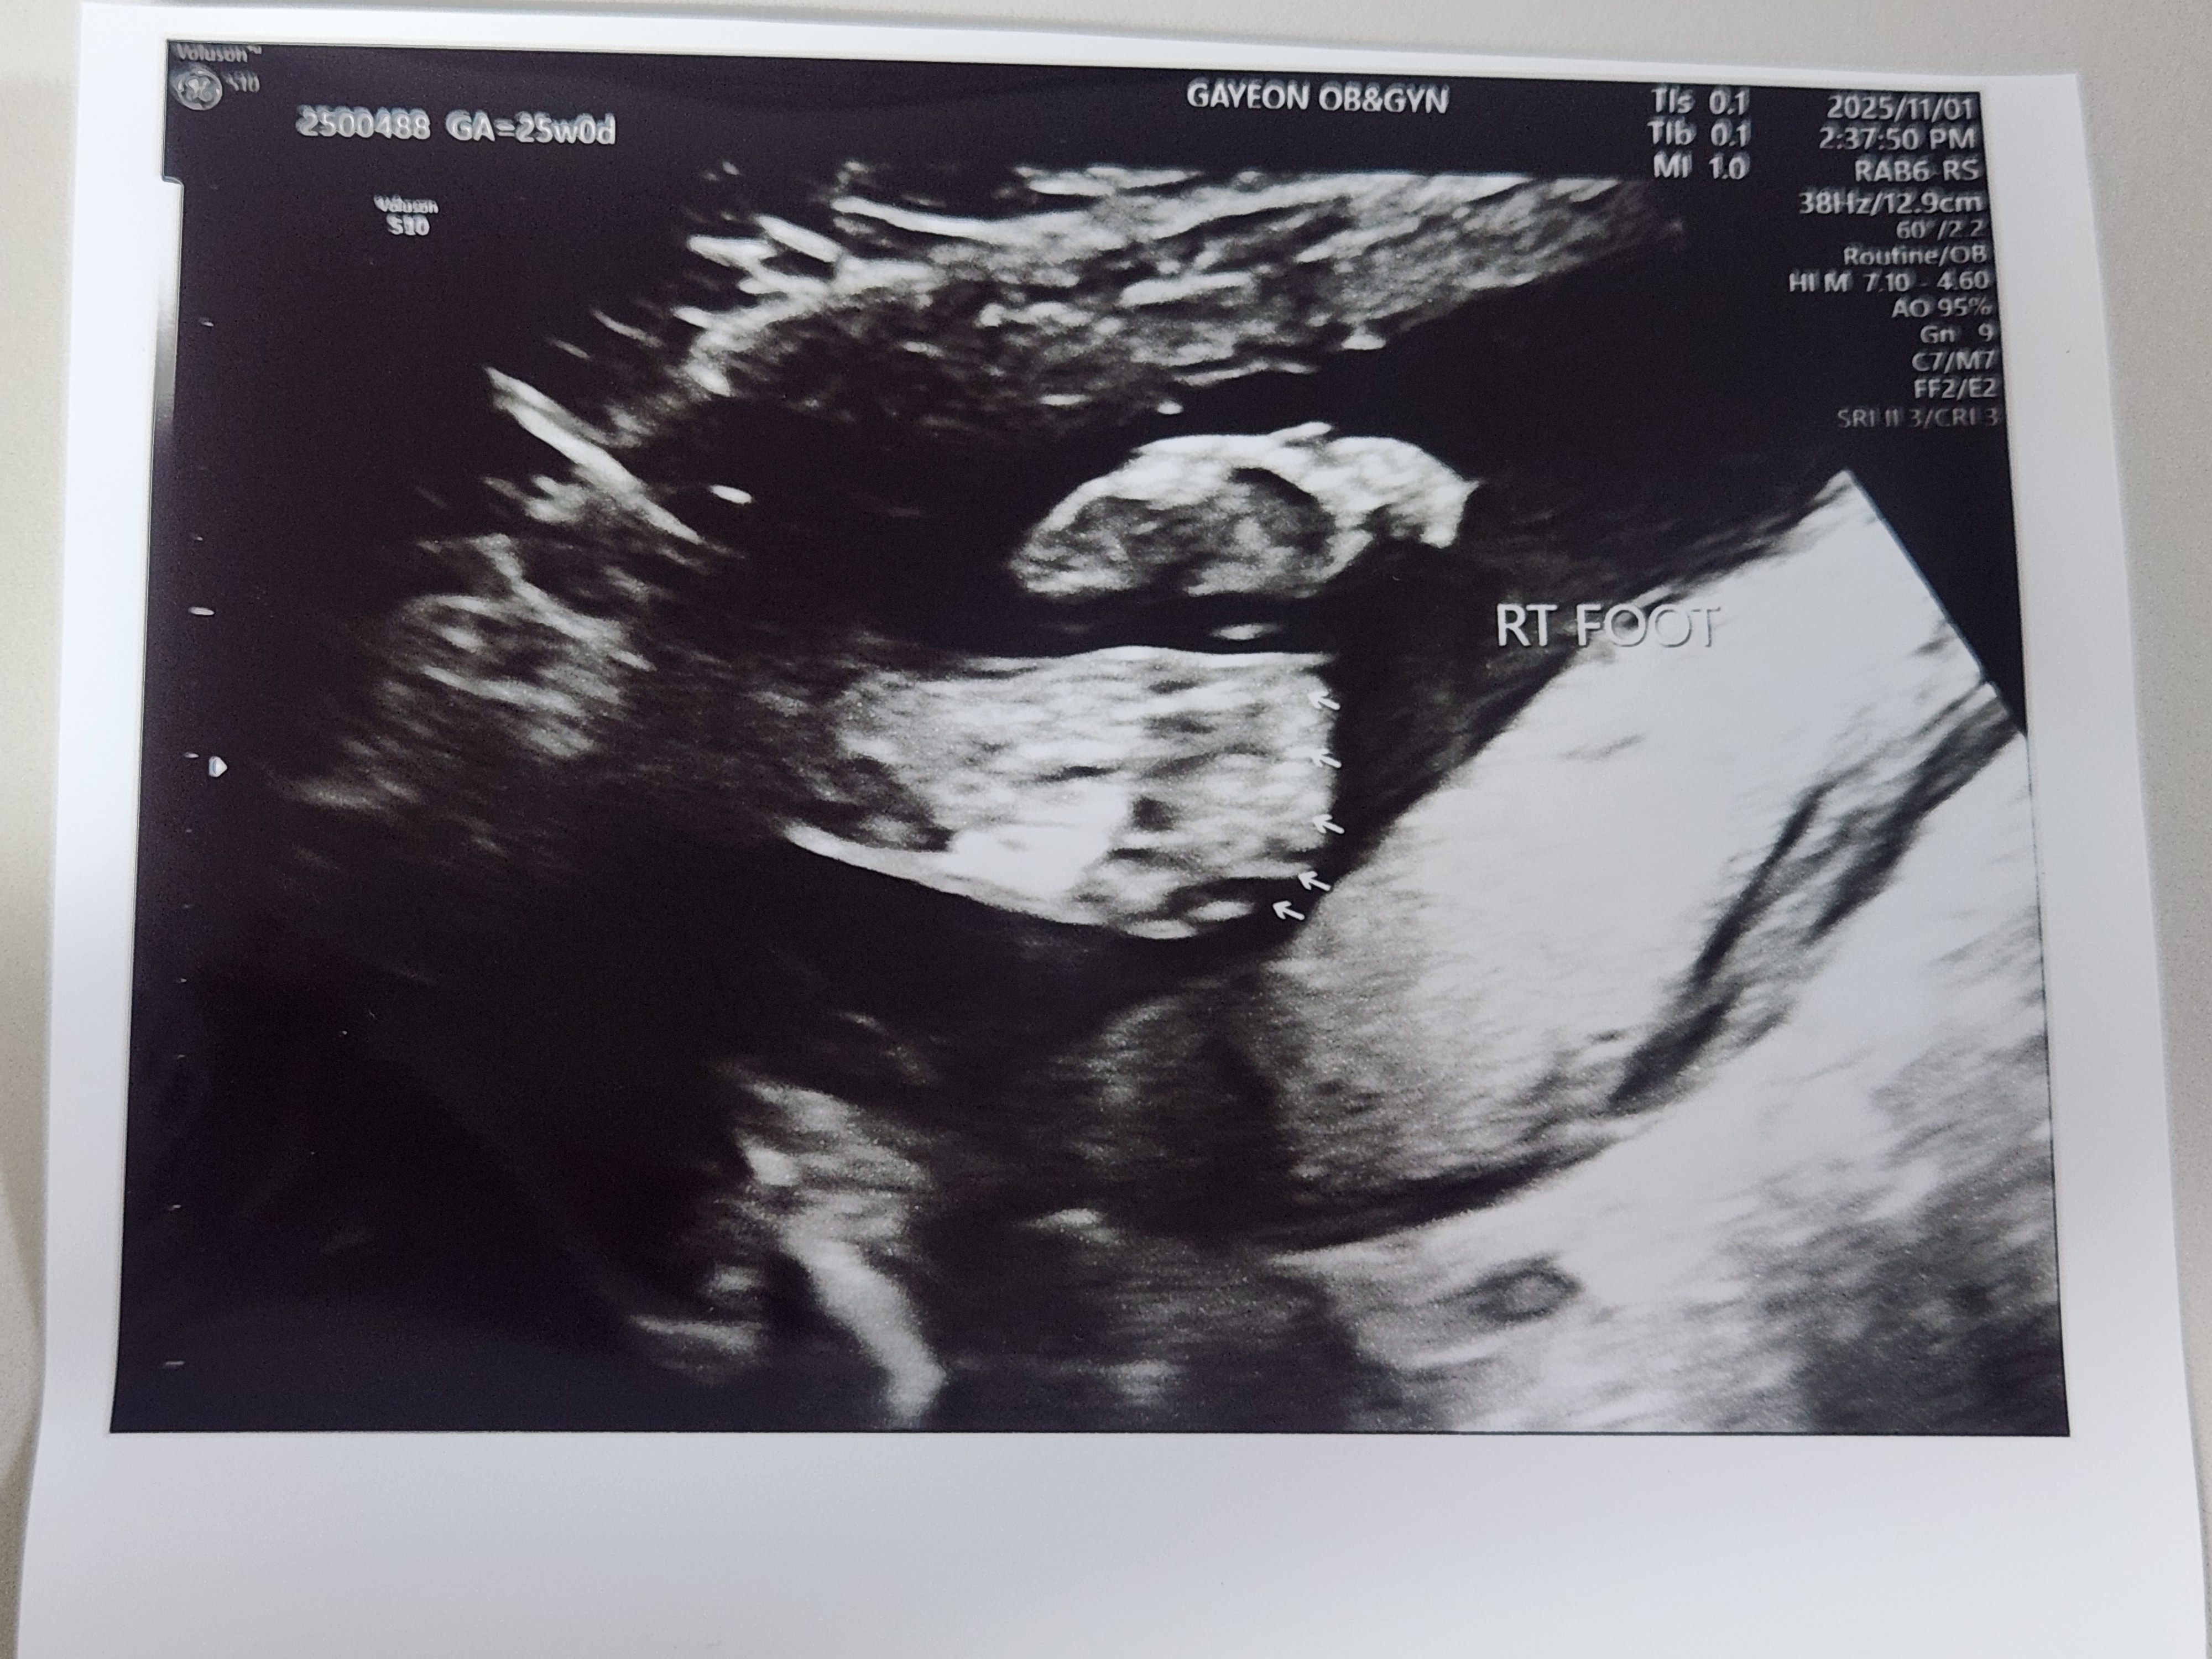

왼쪽 오른쪽 발가락입니다.